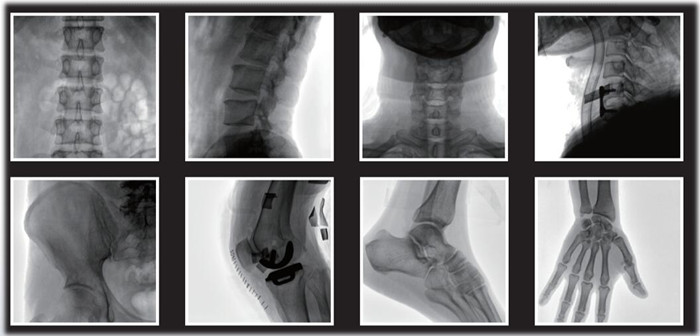

1)小C,骨科手术必备设备,也被称为骨科小C。作为骨科医生的眼睛,能在手术中透视实现准确定位,辅助医生顺利、快速、高效完成手术。目前,小C在我国普及率极高,基本上所有二级及以上医院都标配小C。

小C在骨科的应用是全方位的